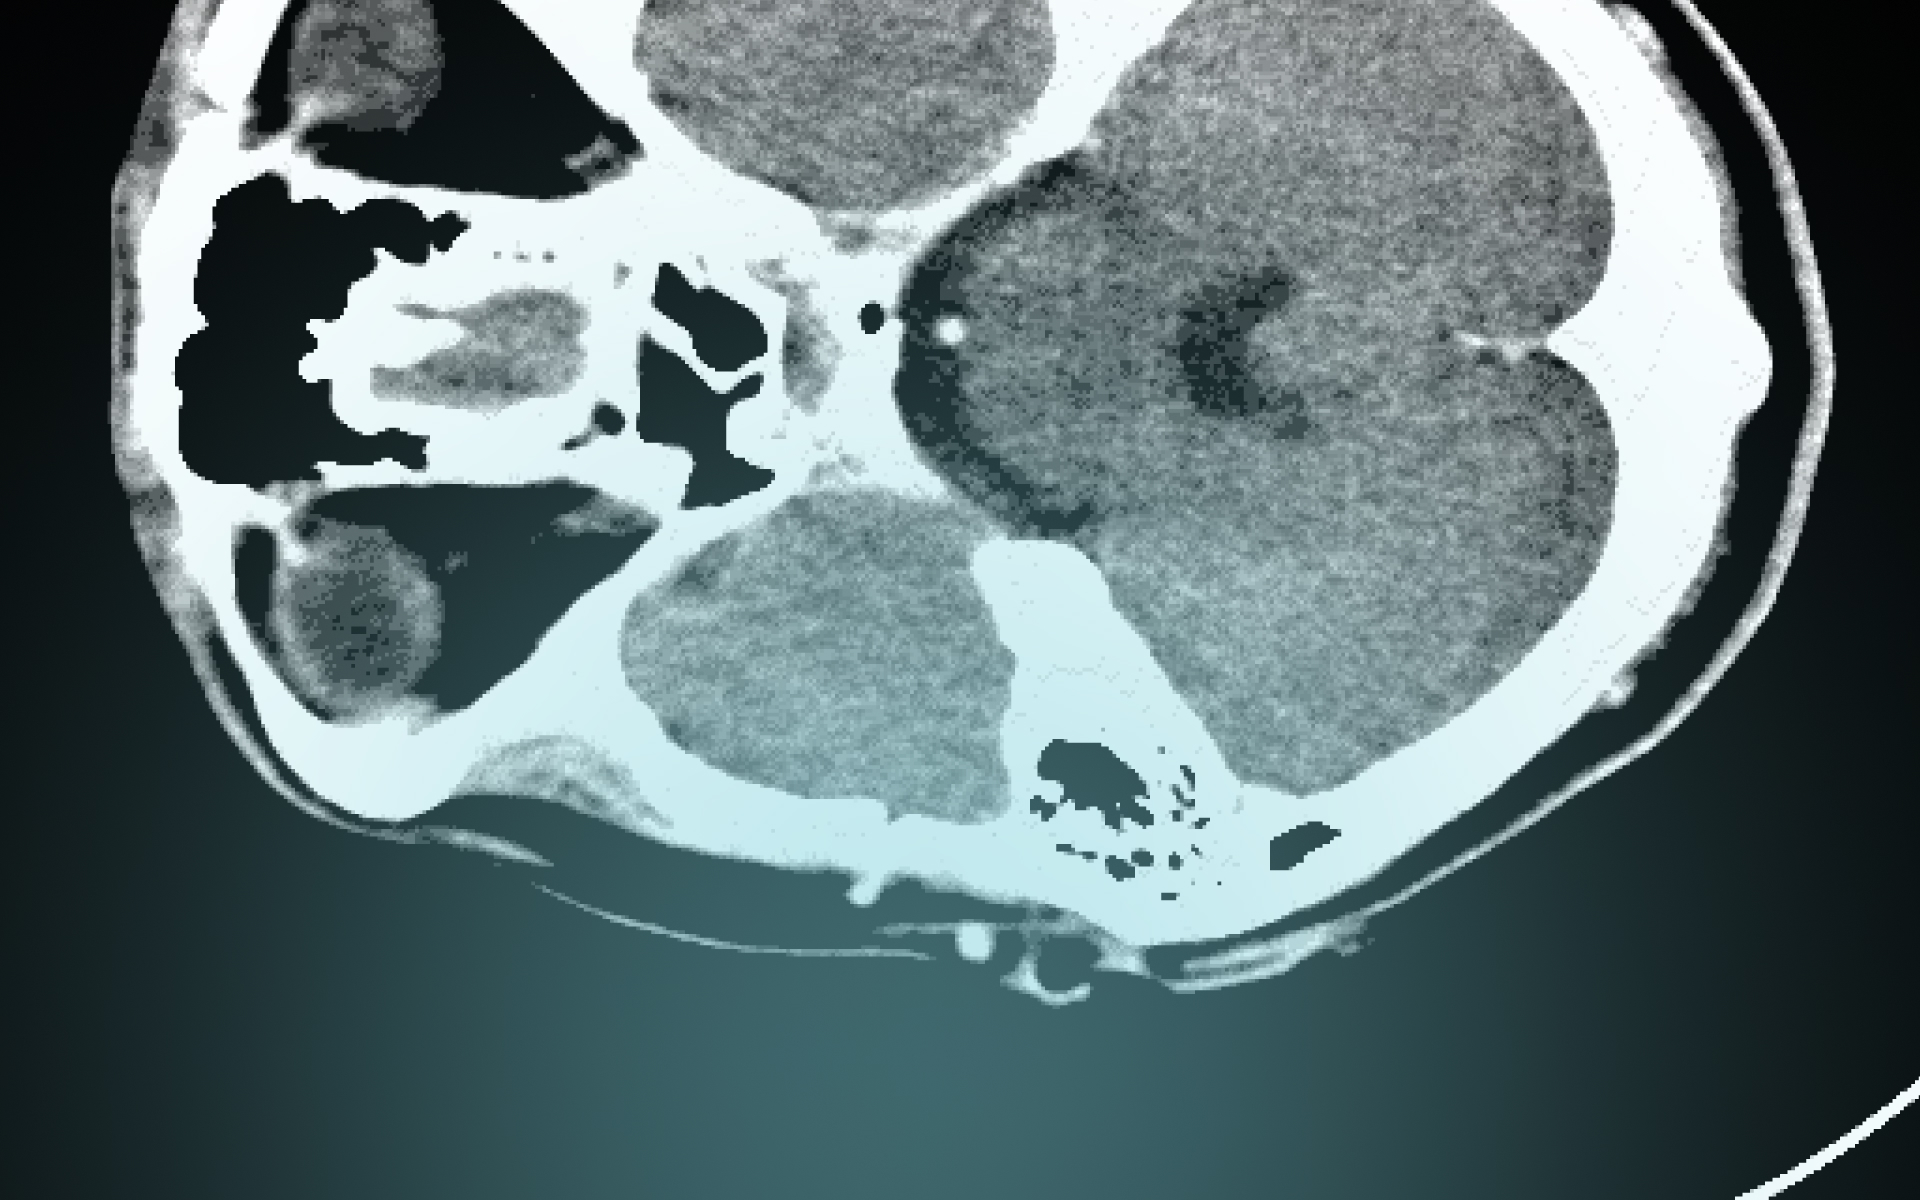

Marc Trabsky and Averyl Gaylor have co-authored a journal article for Social & Legal Studies that examines how radiological images became accepted by courts as visual evidence of death in the 20th century. Initially conceived as a speciality of photography, X-rays confounded courts, eliciting a range of judicial responses, from outright refusal to consider the images as any kind of evidence, to mocking them as cheap parlour tricks for an unwitting public, to recognising them as more reliable than the testimony of the expert witness. The article contends that courts moved towards recognising X-rays as proof of death only by both affirming forensic radiology's promise of ‘mechanical objectivity’ while acknowledging its reliance on the fallibility of ‘human subjectivity’. It suggests that this history has broader implications in socio-legal studies for comprehending how the invention of novel optical techniques continues to problematise legal epistemologies of death in the 21st century.

Post-mortem computed tomography (PMCT) has changed the experiences of bereaved people in coronial investigations. PMCT was developed by the Virtopsy® team initially at the University of Bern, but later at the University of Zurich, in the 1990s. It has been implemented in parts of Australia, Canada, Europe, Japan, UK, and USA since the early 2000s. When the technology is used as a triage tool to decide whether a medical cause of death can be found through CT scanning and an external examination of the body, it can decrease the rate of invasive autopsies in the coronial jurisdiction. For example, when the Victorian Institute of Forensic Medicine, located in Melbourne, Australia, introduced PMCT in 2005, the autopsy rate decreased by approximately 50%, and the rate of objections to autopsies by the next of kin also diminished.

Speaking before forensic scientists, Marc discussed the scope of his project on Virtual Autopsies and explained that post-mortem computed tomography has an important role in enabling coroners to meet the statutory objectives of coronial law, make recommendations for reducing the occurrence of preventable deaths, and carry out the administration of coronial justice.

Marc argued that virtual autopsies are inherently auto-optos, or to put this differently, they create the allure that judicial observers can see the interiority of the corpse with their own eyes. On the one hand, the post-mortem computed tomography appears to be more ‘objective’ than analogue technologies in determining the cause of a death. Yet on the other hand, like the images themselves which compose a body from multiple slices of data, ‘objectivity’ only takes shape through the mediation of mechanical instruments, computational techniques, and the medico-legal expert.